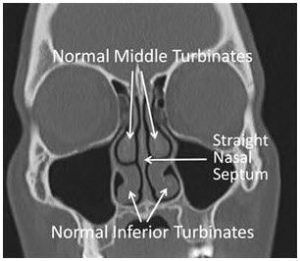

turbinate repair